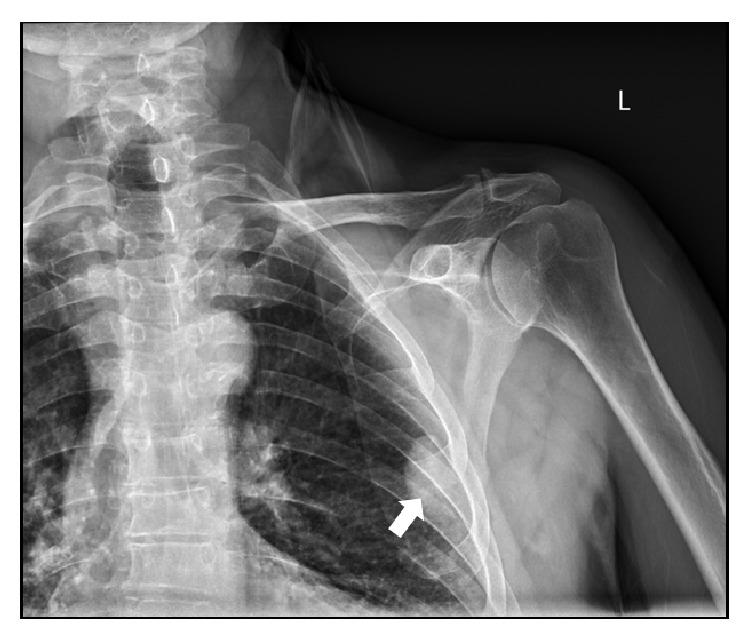

Splenosis is a rare condition that results from the autotransplantation of splenic parenchyma into unexpected locations such as the abdomen or subcutaneous tissue. In the presence of coexisting injury to the diaphragm intrathoracic transplantation can occur emerging as single or multiple pleural-based masses. This occurs after traumatic rupture of the spleen and is usually asymptomatic, only to be discovered incidentally on routine thoracic or abdominal imaging. To our knowledge this is the third documented case of combined intrathoracic and subcutaneous splenosis found in English literature. This occurred in a 71-year-old male involved in a motor vehicle accident at age 19 requiring urgent splenectomy. He has a significant cigarette smoking history and was referred to our hospital for further evaluation of an abnormality seen on shoulder X-ray.